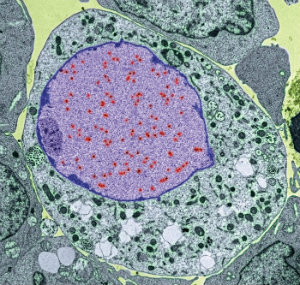

people worldwide, Epstein–Barr Virus (EBV) is a highly successful pathogen. We have co-evolved with this virus over millions of years, achieving a state of détente. EBV infection during childhood, which until recently was the normal state of affairs, usually passes unnoticed. Improvements in living standards mean that, increasingly, infection is delayed until adolescence or later, whereupon EBV infection can cause infectious mononucleosis (glandular fever) with symptoms of fever, sore throat, swollen lymph nodes and a debilitating fatigue that can persist for months. While most people mount a strong immune response able to control their EBV infection, the virus nevertheless establishes a lifelong infection of B cells hidden from the immune system. Periodically, the virus reactivates in some of these cells to complete its life cycle, producing new viruses that are spread to other people via saliva.

However, since its discovery in 1964 in Burkitt’s lymphoma cells, several other cancers have been linked to EBV. In terms of morbidity and mortality two cancers stand out. Nasopharyngeal carcinoma (NPC) is rare in most Western countries but prevalent throughout South East Asia. Some 75,000 cases occur each year, of which almost all are positive for EBV. More recently, EBV has been found in almost 10% of gastric carcinoma tumours. Although the proportion of virus-positive gastric carcinomas is much lower than NPC, there are far more cases of this disease worldwide (an estimated 1 million cases per year). This means that the number of virus-positive cases of these two cancers is actually very similar. EBV is also associated with several different lymphomas, the most common being Hodgkin lymphoma. In total, almost 200,000 cases of EBV-associated cancer occur each year worldwide.